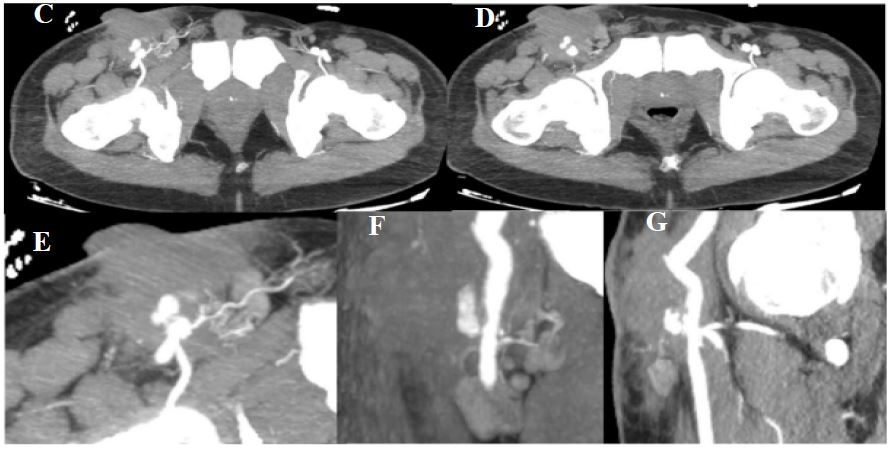

Figure 2: (C to G) MIP CT panels demonstrating the pseudoaneurysm and associated hematoma.

A 55-year-old patient with a history of severe psoriasis and ruptured aortic aneurysm for which he underwent an aortic-bifemoral bypass 2 years ago presented to the emergency department of our hospital with a round pulsatile mass with a palpable thrill fistulised to the skin of the right groin area (Figure 1) where he has been previously operated several times for recurrent anastomotic breakdown without notable improvement. Given the clinical presentation highly suggesting a pseudoaneurysm, a Doppler ultrasound was conducted, revealing a hypoechoic tery with “to and FRO” Doppler flow within the pseudoaneurysm, indicating blood entering and exiting the sac through a narrow neck. The additional examination performed with CTA identified a saccular pseudoaneurysm at the level of the right distal insertion of the anteriorlateral circumferential bypass, measuring 15×14 mm with a neck measuring 7×7 mm. This false aneurysm is contained within a hematoma measuring 72×56 mm (Figure 2). The patient was urgently admitted to the operating room, where he underwent surgical repair for his pseudoaneurysm. The patient is currently still hospitalised at the vascular surgery department and was put under antibiotics as well as treatment for his psoriasis flare-up.

Radiologically, there are multiple vascular imaging modalities with relatively high sensitivity and specificity; these include duplex ultrasound, which is considered the gold standard for the diagnosis of pseudoaneurysms due to its accessibility, low cost and non-invasiveness; it allows the assessment of blood flow within the femoral veins and arteries, the pseudoaneurysm and its communicating tract [3]. It typically reveals a round anechoic or hypoechoic pulsatile mass contiguous to the artery with a “to and FRO curve” Doppler flow formed by the systolic and diastolic in- and outflow of blood from the PSA [3]. Duplex Ultrasound has a sensitivity and specificity of 94–99% and 94– 97%, respectively [3], hence allowing the diagnosis with high accuracy, but in some cases, further examination with Computed tomography and magnetic resonance angiography may be required for complex origins or retroperitoneal location [3]. On CTA, PSA presents as a well-defined, contrast-enhancing outpouching adjacent to the arterial wall, connected to the parent artery through a narrow neck; it may have a saccular or fusiform shape and appear as a contrast-filled cavity. PSAs could also be surrounded by hematomas or soft tissue oedema, especially in case of a recent rupture or infection.